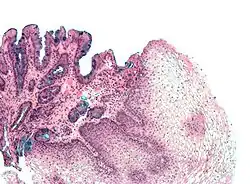

Histologische Kriterien

Zur weiteren Diagnosestellung werden umfangreiche Gewebeproben (Biopsien) aus den auffälligen Schleimhautstellen genommen und in der Pathologie mikroskopisch untersucht. Hier wird zum einen festgestellt, ob eine Umwandlung von Gewebe zu Zylinderepithel vorliegt und zum anderen der Nachweis bestimmter Zellen, der Becherzellen, gefordert. Diese sind typisch für das Epithel des Dünndarms, nur dann kann von einer intestinalen (von lat. Intestinum, Darm) Metaplasie gesprochen werden.[3] Selten können in einer Barrett-Metaplasie auch andere Zellen des Verdauungstraktes vorkommen, darunter Paneth-Zellen, neuroendokrine Zellen und Zellen der Bauchspeicheldrüse.[6]

Einen weiteren Punkt, der in der mikroskopischen Untersuchung zu klären ist, bildet die Klassifizierung von Gewebeschäden. Genauer geht es um die Frage, ob sich bereits ein bösartiger Tumor oder eine Vorstufe davon (Dysplasie) gebildet hat. Diese Vermehrung geschädigter Zellen wird zusammenfassend als „Neoplasie“ bezeichnet. Die Einteilung der Neoplasien erfolgt nach der Wien-Klassifikation in Gewebe ohne Dysplasie, Gewebe mit möglicher Dysplasie, Gewebe mit gut differenzierter Dysplasie (Low Grade Dysplasie), Gewebe mit schlecht differenzierter Dysplasie (High Grade Dysplasie) sowie Gewebe mit einem Adenokarzinom (nicht invasiv oder möglicherweise invasiv). Nach dieser Einteilung richtet sich die weitere Therapie.[3]